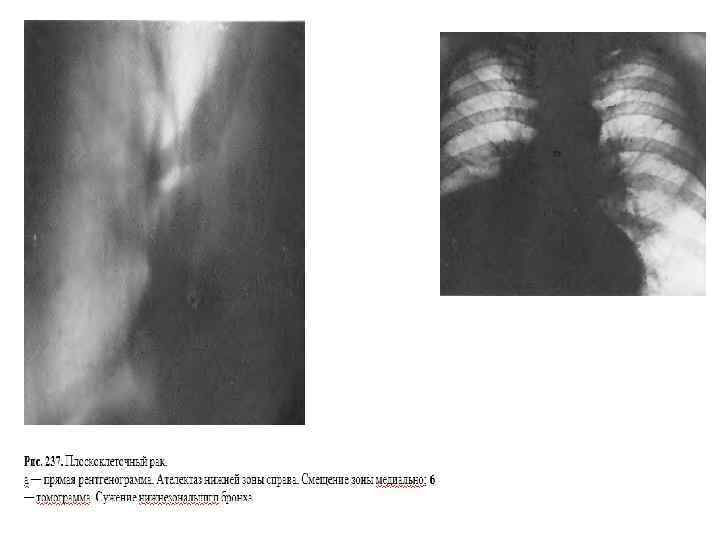

Среди всего многообразия гистологических форм рака легкого с точки зрения рентгенолога целесообразно выделить 3 типа: 1) Плоскоклеточный рак наиболее типичная в нашей республике гистологическая форма (около 70% всего рака легкого), поражающая главным образом мужчин, опухоль с умеренными темпами роста, обычными этапами метастазирования в лимфоузлы, с типичной для рака легкого склонностью к отдаленному метастазированию в органы мишени. Именно о плоскоклеточном раке идет речь, когда мы рассматриваем «классическую» традиционную рентгенодиагностику рака легкого. 2) Аденокарцинома внешне «похожая» на плоскоклеточный рак опухоль, имеющая зачастую клинико биологические особенности, позволяющие называть ее « непредсказуемой» или «коварной» опухолью. 3). Недифференцированный рак. Большую часть этой группы составляет мелкоклеточный рак одна из наиболее злокачественных опухолей организма человека. С точки зрения лучевой диагностики, эта форма рака манифестирует бурно прогрессирующим лимфогенным метастазированием. На фоне массивных конгломератов лимфоузлов трудно обнаружить первичную опухоль, из за быстрого развития поражения зачастую сужение бронхов и нарушение вентиляции не успевают развиться, в связи с чем возникают трудности при дифференциальной диагностике недифференцированного рака и лимфомы средостения. Эта опухоль также склонна к быстрому отдаленному гематогенному метастазированию в головной мозг, печень, почки, кости, надпочечники.

Повышенное внимание уделяется анализу структуры опухолевой тени с целью выявления участков распада в ней. Распад опухоли при центральном раке явление относительно редкое, но потенциально очень опасное для больного в связи с вероятностью развития смертельного профузного легочного кровотечения. Следует рассматривать таких пациентов как нуждающихся в неотложной хирургической помощи, максимально ускорять их обследование и срочно направлять к торакальным хирургам онкологам. Полости распада в опухолевом узле бывают двух видов: а) расположенные на периферии большого перибронхиального узла б) расположенные центрально, являющиеся как бы продолжением пораженного бронха и дренируемые им. Именно этот вид распада является потенциально наиболее угрожающим в отношении кровотечения. В заключение заметим, что подвергаются распаду почти исключительно центральные плоскоклеточные раки.